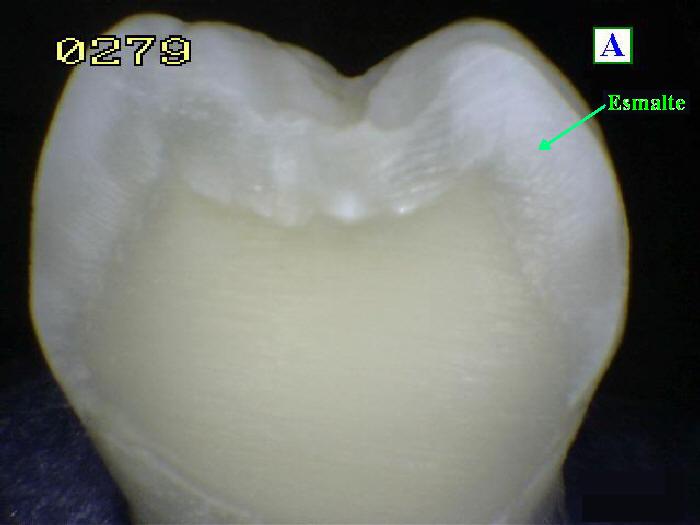

Esmalte

dental El esmalte es la sustancia más

dura y altamente mineralizada del cuerpo. Tiene

su origen en el ectodermo oral. Es uno de los

cuatro tejidos principales que conforman el

diente, junto con la dentina, el cemento y la

pulpa dental. [6] Normalmente es visible y debe

estar respaldado por dentina subyacente. El 96%

del esmalte está compuesto por minerales, con

agua y material orgánico que comprende el resto.

[10] La gran cantidad de minerales

en el esmalte explica no solo su resistencia

sino también su fragilidad. [8] La dentina, que

es menos mineralizada y menos frágil, compensa

el esmalte y es necesaria como soporte. [10] A

diferencia de la dentina y el hueso, el esmalte

no contiene colágeno. Las proteínas notables en

el desarrollo del esmalte son las ameloblastinas,

las amelogeninas, las esmalte y las tuftelinas.

Se cree que ayudan en el desarrollo del esmalte

al servir como soporte marco, entre otras

funciones. [11] En raras circunstancias, el

esmalte puede no formarse, dejando la dentina

subyacente expuesta en la superficie. [12]